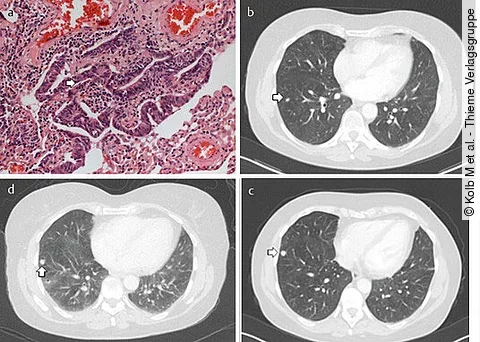

Pneumo-Quiz: Asthma-Patientin mit obstruktiven Atembeschwerden

Die 59-jährige Patientin gibt an, zunehmende Atembeschwerden zu haben. Sie weiß von einer Asthma-Erkrankung, die seit vielen Jahren therapiert wird, und ist Nichtraucherin.